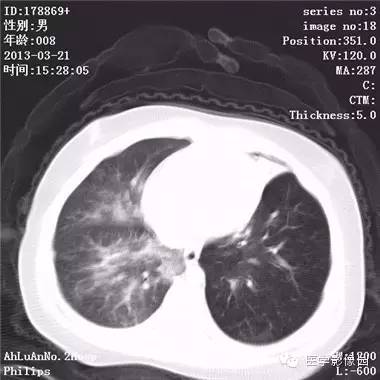

患儿男,8个月,呛咳,发热一周。实验室检查白细胞及中性粒细胞增高。

两肺肺纹理增多、增粗,右肺可见斑片状、片絮状模糊影,边界欠清;左肺上叶见楔形高密度影,内可见支气管征,尖端指向肺门;左肺下叶肺野透亮度增强;另见左肺主支气管内可见块状软组织密度影。

支气管异物(花生米)伴两肺炎症(追问病史,患儿奶奶层于一周前喂食患儿花生米,当时疑似“呛进去”,后来见好了也就没留意)。